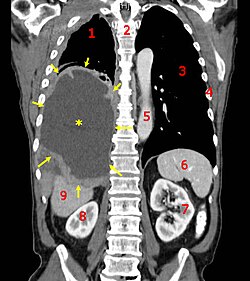

Oncology is a type of medicine that takes care of people who have cancer. Cancer is a sickness in the body where cells keep growing and multiplying when they should not. Oncologists are doctors who specialize in treating cancer and helping people who have it. They use different ways to fight the cancer, like surgery to take out tumors, chemotherapy to help stop cancer cells, and radiation to target cancer cells directly. Oncologists also help people with cancer by talking to them about their options and making sure they get the best treatments for their situation.